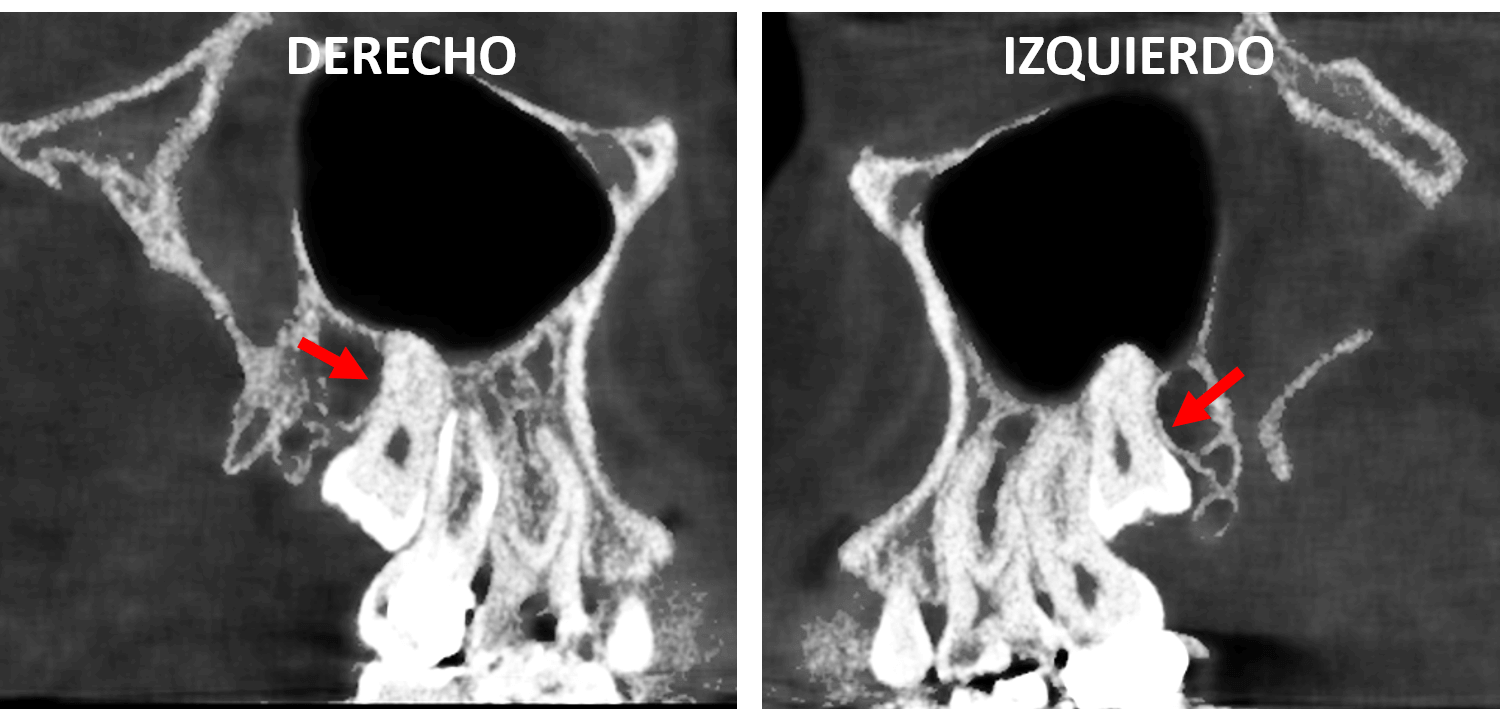

En cortes coronales (Fig.4) se observan de forma bilateral la impactacion bilateral de los terceros molares superoriores, con la corona parcialmente erupcionada y las raíces en estrecha relación con el piso del seno maxilar.